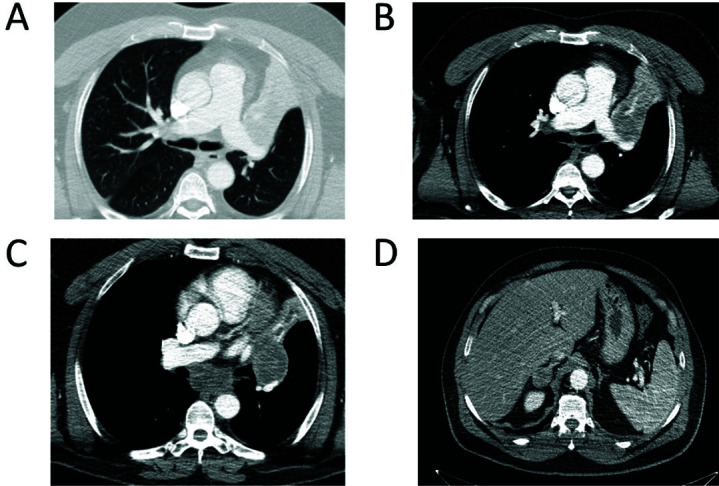

The advent of immunotherapy, and in particular the use of immune-checkpoint inhibitors, has profoundly revolutionized the treatment of different cancers, including lung cancer. The use of immune-checkpoint inhibitors has prolonged survival in lung cancer with a strong benefit in a significant percentage of patients with non-small-cell lung cancer. Here, a clinical case of a patient who, despite testing negative for PD-L1, displayed a sustained complete response to immunotherapy treatment in advanced metastatic non-small-cell lung cancer is presented. Additionally, recent findings concerning the application of immunotherapy in this context are reviewed.

Abstract Image